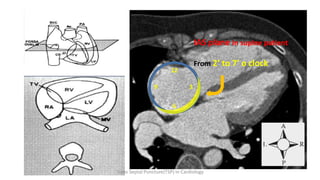

IAS plane in supine patient

From 2’ to 7’ o clock